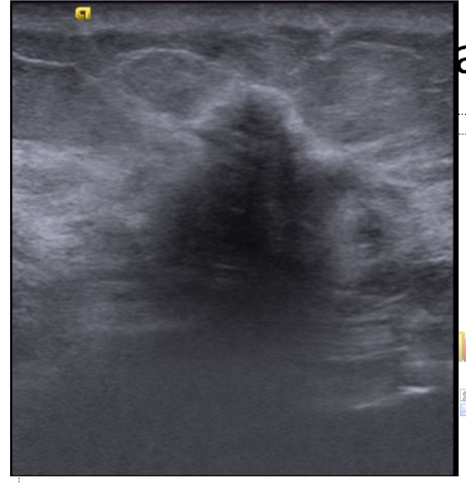

Figure 1- MLO (a) and CC (b) screening mammogram of the right breast with heterogeneous dense breast parenchyma shows a heterogeneous dense spiculate mass in lower inner quadrant (better seen on CC views; white arrow in figure 1b ). Figure 2 : Ultrasound shows a hypoechoic mass with spiculate margins, non parallel orientation and posterior acoustic shadowing. Figure 3: CEMRI reveals an irregular heterogeneous enhancing mass in lower inner quadrant (white arrow in figure 3a, c) and an additional small irregular heterogeneous enhancing mass in the upper inner quadrant (red arrow in image 3a, c) . Figure 4: Second look ultrasound revealed a hyperechoic mass with mild heterogeneity and indistinct margins which was not clearly appreciated with normal compression (figure 4a) and is better appreciated with excessive focal compression (figure 4b) . USG guided biopsy is performed as the mass was suspicious on CEMRI. Final histopathology for the second lesion - IDC